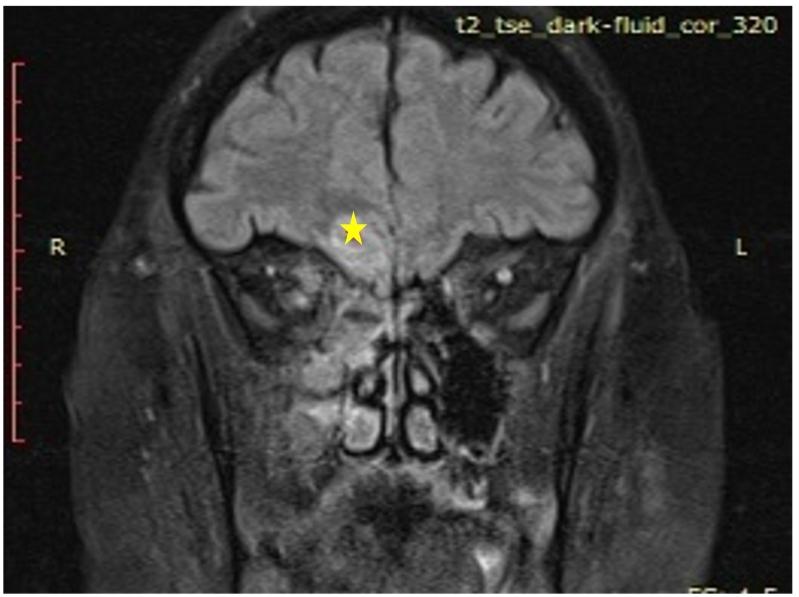

CASE PRESENTATION

we report two cases of brain abscess as a complication of nasopharyngeal COVID-19 testing. The first case was of a 47-year-old male diabetic patient with a positive medical history for immune thrombocytopenic purpura (ITP) who developed a frontal brain abscess one week after the swabbing procedure and was treated with systemic antibiotics followed by a successful functional endoscopic sinus surgery. The second case involved a hypertensive female patient in her 40s who also developed a frontal brain abscess on the same side as painful nasal COVID-19 testing. Systemic antibiotics were used to treat the patient.

我们报告两例因新冠病毒鼻咽检测引发脑脓肿并发症的病例。首例为一名47岁男性糖尿病患者,有免疫性血小板减少性紫癜(ITP)病史,在拭子采样操作一周后发生额叶脑脓肿,接受全身抗生素治疗,随后成功进行了功能性鼻内镜鼻窦手术。第二例涉及一名40多岁的高血压女性患者,在进行痛苦的新冠病毒鼻咽检测后,同侧也发生了额叶脑脓肿。对该患者使用了全身抗生素进行治疗。